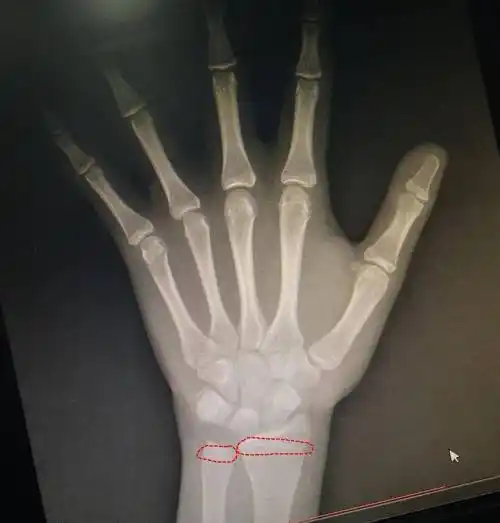

14岁男孩身高153,检查后医生:骨骺线已闭合,最多还能长2-3㎝

14岁男孩骨龄16岁,还能长高多少?主要看骨骺线的闭合情况!

如何确诊指骨骨骺早闭?